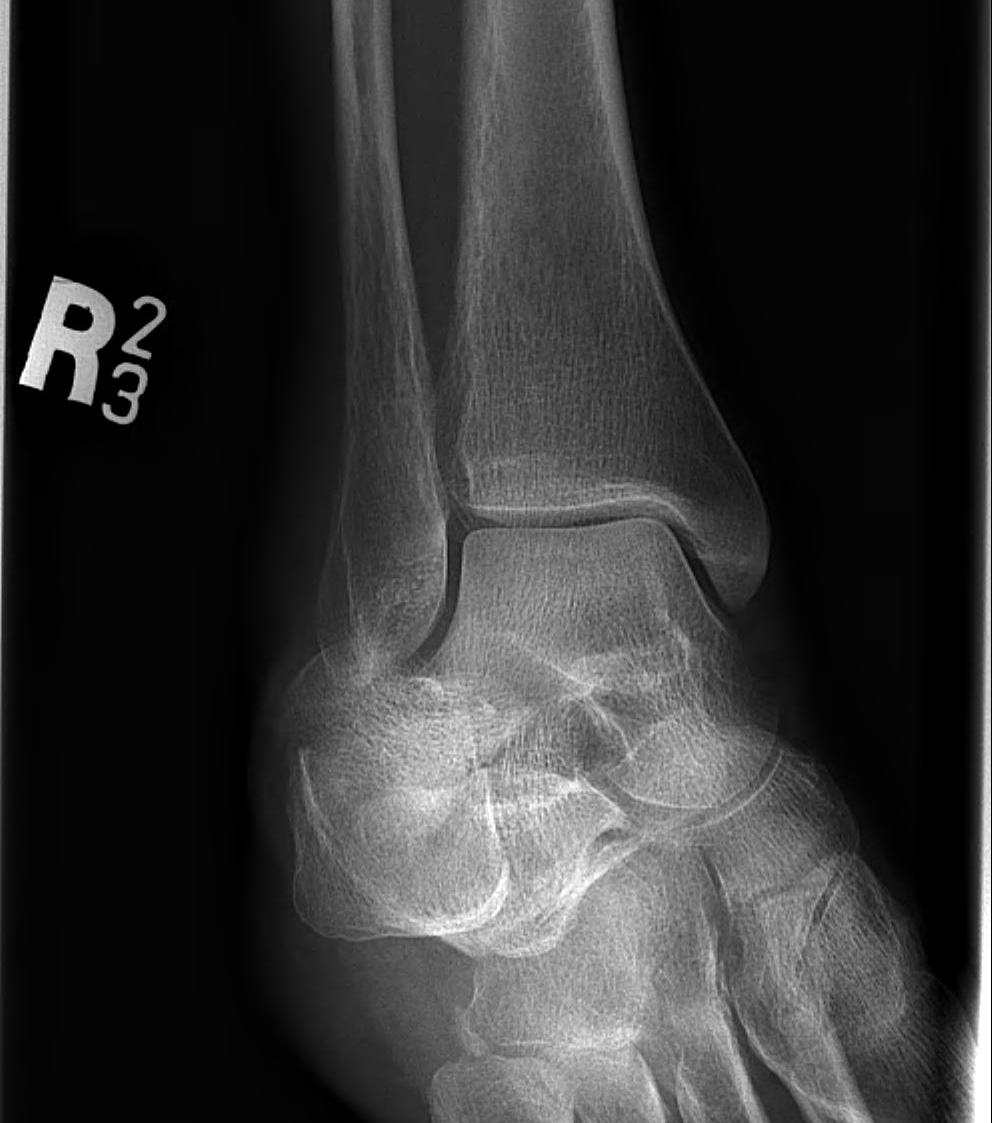

X-ray assessment

3 standard views

AP / Lateral / Mortise

Mortise

- AP with foot internally rotated

- should be symmetrical space around talus

| Increased tibio-fibular clear space | Overlap | Increased medial clear space |

Medial border of the fibula Lateral border of the posterior tibia (incisura fibularis) Measured 1 cm above the plafond |

Overlap of the fibula and the anterior tibial tubercle

Medial talus to lateral medial malleolus |

| <5mm AP and mortise |

> 6 mm AP view > 1 mm mortise view |

< 4mm Equal to superior clear space |

| Syndesmotic injury | Syndesmotic injury |

Deltoid ligament injury Lateral talar shift |

Lateral talar shift / increased medial clear space / deltoid ligament injury

Tibia / fibular overlap < 1mm / syndesmotic injury